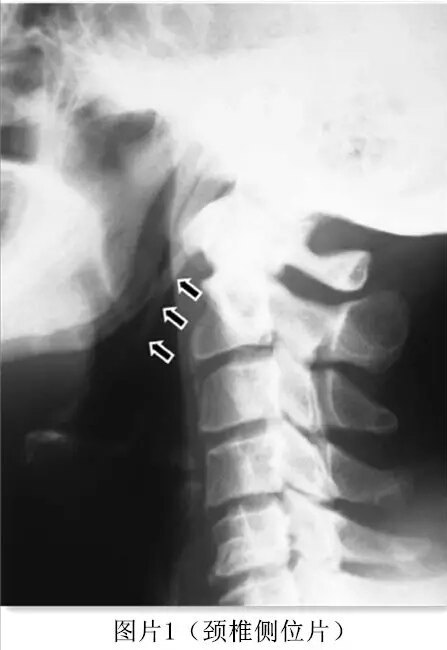

一名51歲的糖尿病男性患者,頸部疼痛,疼痛放射到右上肢,持續(xù)6個月。使用非甾體類鎮(zhèn)痛藥治療,情況未見改善,并持續(xù)惡化。一般體格檢查均表現(xiàn)正常,除了下頜下區(qū)域呈局部壓痛。血常規(guī)、尿常規(guī)檢查均提示正常。頸椎側(cè)位片懷疑患者莖突過長(Elongatedstyloid process)(圖1)。 在CT掃描中,右側(cè)莖突(55 mm)比左側(cè)莖突(52 mm)稍長(圖2)。并發(fā)現(xiàn)柱狀韌帶鈣化(如箭頭所示)。病人被轉(zhuǎn)診于醫(yī)院耳鼻喉科。局部注射類固醇和利多卡因后,癥狀完全緩解。 莖突長度超過30 mm被稱為Eagle綜合征,其臨床癥狀通常歸因于莖突過長導(dǎo)致咽、頸神經(jīng)或血管相互作用。這些癥狀是非特異性的,可以與多種疾病混淆,包括面部神經(jīng)痛、口腔、耳、顳下頜關(guān)節(jié)和脊椎疾病等。臨床上觸診莖突尖端可加重現(xiàn)有癥狀的表現(xiàn),但三維CT掃描是莖突綜合征最有價值的診斷工具。 在對莖突綜合征(Eagle's syndrome)進行了一定的了解以后,接下來簡要的介紹和學習一下莖突綜合征(Eagle's syndrome)相關(guān)內(nèi)容。 莖突綜合征(Eagle's syndrome)是因莖突長度過長或位置、形態(tài)異常,或莖突舌骨韌帶發(fā)生鈣化、骨化,壓迫和刺激鄰近血管、神經(jīng)而引起的咽部異物感、咽痛、反射性耳痛、頸部疼痛、頭暈、偶有伴發(fā)暈厥和流涎增加等癥狀的總稱。當頭頸部轉(zhuǎn)動或作吞咽、發(fā)音等動作時,其癥狀會誘發(fā)或加重。 莖突綜合征常見于成年人,是耳鼻咽喉科常見病之一,其臨床癥狀表現(xiàn)較為復(fù)雜,易與慢性咽喉炎、咽異感癥、舌咽神經(jīng)痛、咽部及舌根早期腫瘤等疾病相混淆。對于莖突綜合征的診斷主要依靠患者主訴、臨床觸診和影像學手段三種方式來完成。 對于臨床醫(yī)生來說,掌握除儀器檢查以外的體格檢查能力是具有一定意義的,而針對莖突綜合征患者臨床的觸診是需要了解的。對此做一下簡單的介紹:囑咐被檢查者保持正坐位,頭略上抬,操作過程中操作者戴無菌手套,以右手食指觸右側(cè)扁桃體窩,左手食指觸診左側(cè)扁桃體窩。觸診扁桃體的前、后、上、下四個部位,如觸到堅硬條索或骨性刺狀突起,并且患者感受此處為不適之處,可誘發(fā)導(dǎo)致咽痛或咽痛加重,即為過長的莖突。操作過程中要防止患者受刺激后,閉合口腔造成損傷,可以在觸診前對所檢查的患者咽部噴以1%利多卡因以減輕咽部刺激性反射,注意操作前與患者做好溝通交流工作。 莖突綜合征的影像學方面內(nèi)容,主要包括X線和CT兩種常用檢查方法。其中針對莖突綜合征的診斷,較常用的是X線法。但X線分辨率較低,加上頸部及顱底解剖結(jié)構(gòu)較復(fù)雜、莖突形態(tài)個體的差異性較大,使拍攝角度不宜掌握,致使數(shù)據(jù)測量的準確性受到影響,造成診斷符合率偏低。而CT檢查尤其是CT三維重建技術(shù),能夠測量得出莖突長度、前傾角度及內(nèi)傾角度,更為準確反映其特征。CT檢查缺點就在于價格較高。影像學診斷,需要熟知莖突長度、形態(tài)、位置等內(nèi)容,這對于耳鼻喉科醫(yī)生來說較困難,但熟悉莖突的長度測量是一種較為簡單的方式,國內(nèi)一般以自莖突尖端至莖突根部中點的連線超過25mm,可以考慮莖突綜合征的可能。 莖突綜合征的非手術(shù)治療方法一般采用鎮(zhèn)痛或局部注射類固醇,但目前普遍認為莖突過長主要的治療方法為截短莖突。 莖突截短術(shù)有兩種手術(shù)徑路,口咽徑路和頸外徑路兩種。 1、口咽徑路適用于扁桃體窩內(nèi)觸及莖突的患者,其優(yōu)點為尋找莖突容易,損傷小,出血少,傷口愈合程度與扁桃體手術(shù)相似; 2、口外徑路一般從下頜角下方處作切口,莖突及周圍組織結(jié)構(gòu)可以充分暴露,易在上頜動脈和顳淺動脈的分叉部找到莖突的準確位置,且術(shù)后并發(fā)癥相對較少。 另外中醫(yī)藥治療也是一種有效的方法,在減輕疼痛和不適感方面具有療效。但如果莖突綜合征導(dǎo)致的臨床癥狀反復(fù)發(fā)作,手術(shù)治療是唯一方法。